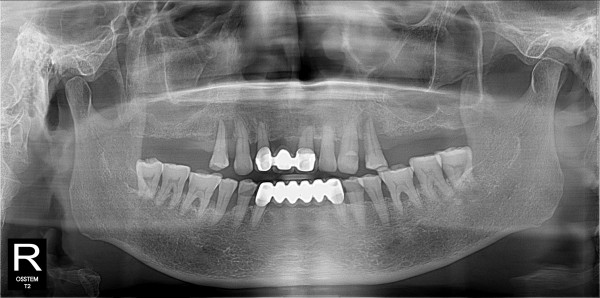

구치부 임플란트 최고관리자 0건 23-11-07 18:30 본문 구치부 임플란트 + 전치부 크라운 목록 이전글구치부 임플란트 23.11.07 다음글구치부 임플란트 23.11.07 댓글목록 0 댓글목록 등록된 댓글이 없습니다.